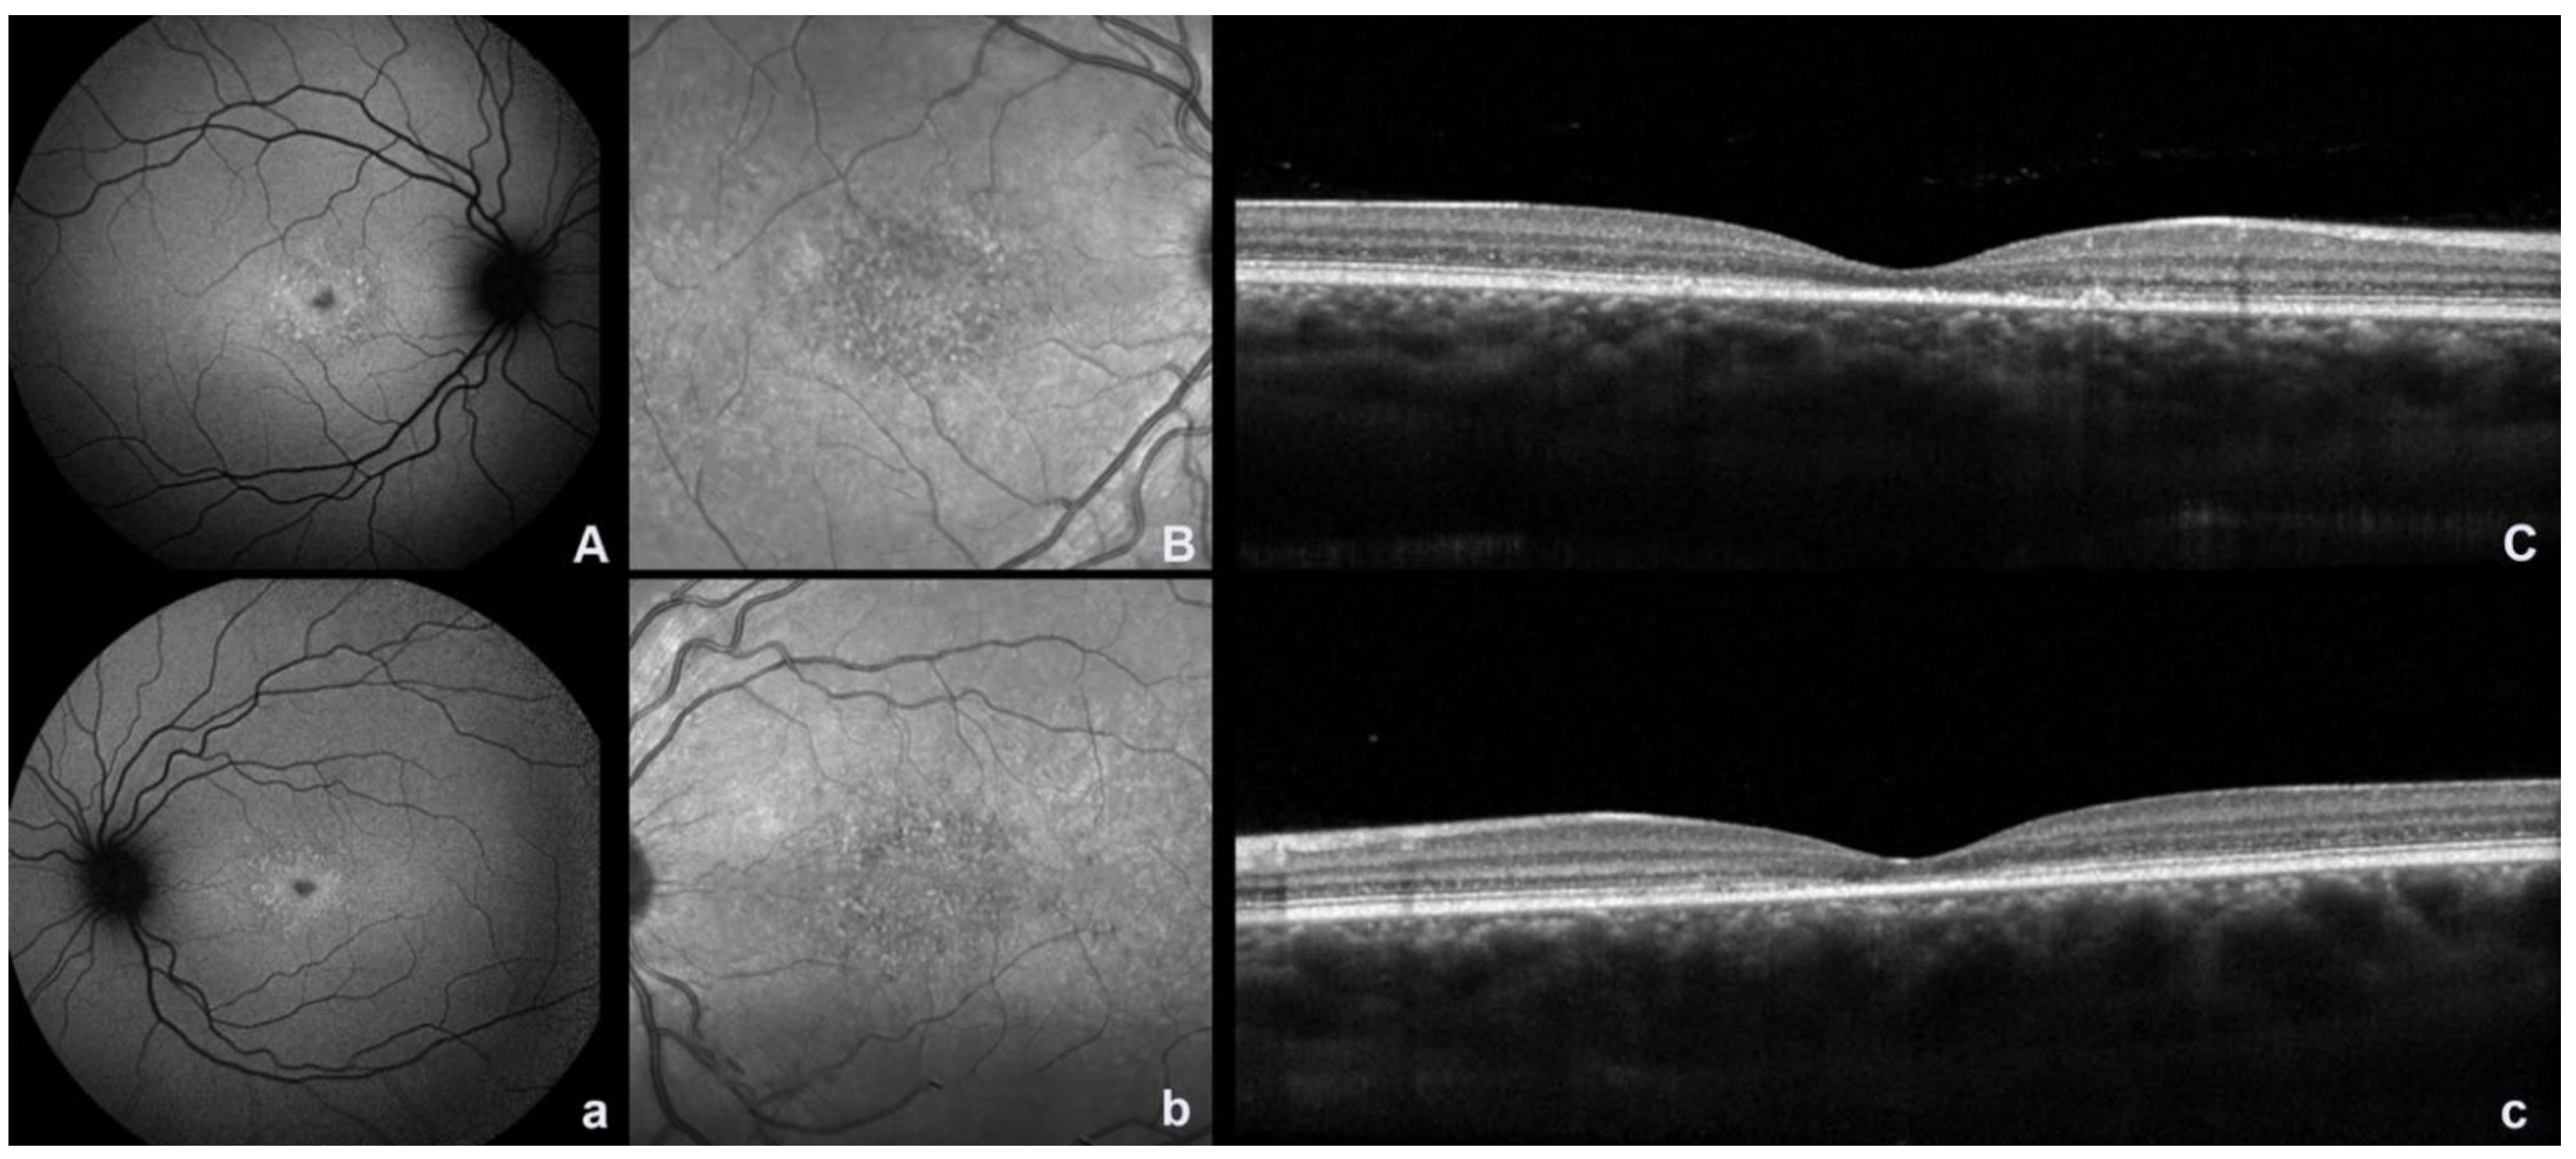

2. Fundus Autofluorescence and Near Infrared Autofluorescence

4. Optical Coherence Tomography Angiography and Spectral Domain Optical Coherence Tomography

5. Hyperreflective Foci